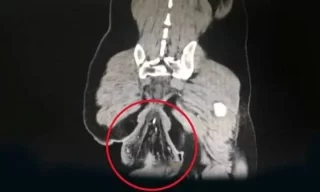

Ânus de homem cai após ele ficar na privada com celular por meia hora

O diagnóstico foi de prolapso retal, uma condição rara e grave em que a parte final do intestino grosso perde sua sustentação